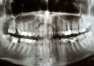

Diagnostyka obrazowa jest nieocenionym źródłem wiedzy na temat tego, co na ogół jest ukryte przed ludzkim wzrokiem. Panorama zębów stanowi nieodłączny element kompleksowego leczenia zębów. Pomaga spojrzeć holistycznie na stan uzębienia, dlatego stomatolodzy często zalecają wykonanie zdjęcia pan tomograficznego przed rozpoczęciem leczenia. Podpowiadamy jak wygląda prześwietlenie zębów oraz czy jest bezpieczne dla zdrowia.

Prześwietlenia zębów wykonuje się na kilka sposobów, a wśród RTG punktowego oraz cefalogramu, zdjęcie panoramiczne jest najdokładniejsze i najszersze. Swoim zasięgiem obejmuje całą szczękę wraz z górnym ora dolnym rzędem zębów. Takie szerokie spektrum ujęte na zdjęciu panoramicznym pozwala dentyście ocenić stan zębów, dużo dokładniej niż w przypadku oględzin gołym okiem. RTG stomatologiczne wykonane pantomografem pozwala otrzymać dokładny obraz zębów oraz kości szczęki, żuchwy i stawów skroniowo-żuchwowych, jak również zatok szczękowych. Dzięki temu lekarz stomatolog może ustalić przyczynę problemu oraz wdrożyć odpowiednie leczenie zębów.